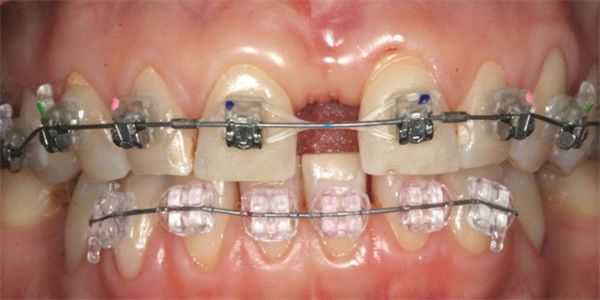

- Брекеты. Это несъёмные конструкции для перемещения зубов. Обычно брекеты применяют при больших диастемах, но они подходят в качестве лечения только после прорезывания всех постоянных зубов. Металлические брекеты самые доступные по цене, сапфировые и керамические дороже, но они более эстетичные.

Ортодонтическое лечение. Если нарушено строение всей зубочелюстной системы, выполняют лечение брекетами или капами, чтобы выровнять его. Лечение планируют так, чтобы увеличенный межзубный промежуток «закрылся» после коррекции положения.

Ортодонтическое лечение. Может выполняться с помощью брекет-системы или капы. Для коррекции используют направленное малое усилие — резцы перемещаются медленно, промежуток закрывается постепенно. Ортодонтическое лечение используют при неправильном положении зубных корней, если появление диастемы связано со строением зубочелюстной системы.